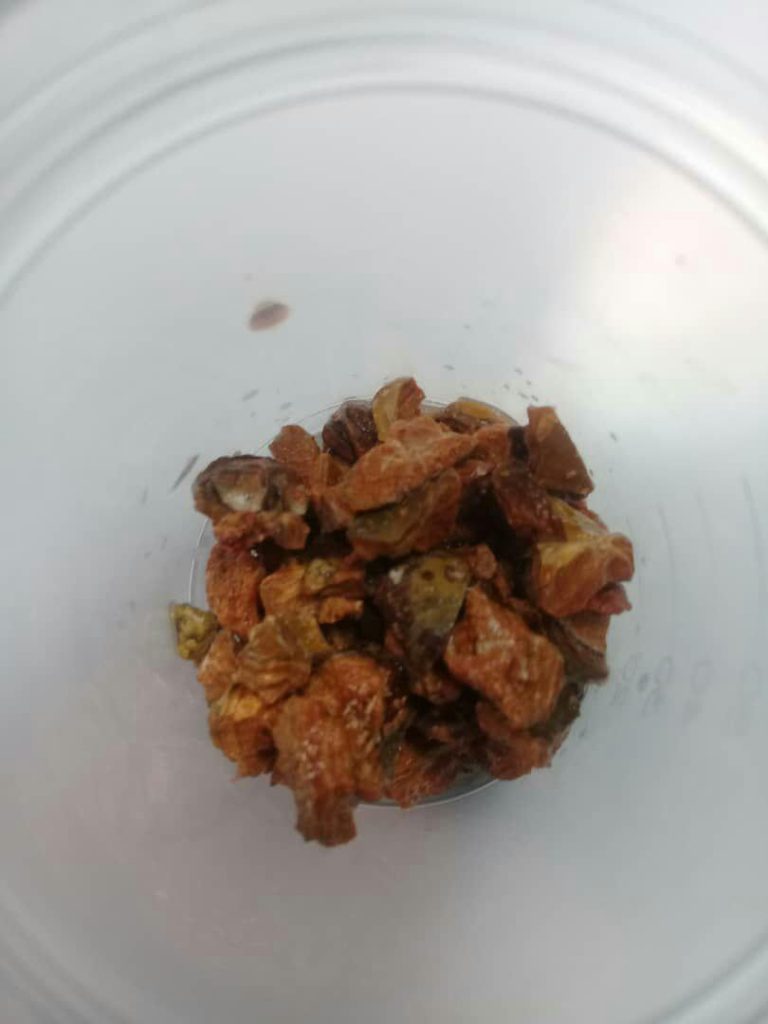

جراحی سنگ به روش بسته و PCNL

- درمان سنگ کلیه

- از بین بردن سنگ کلیه